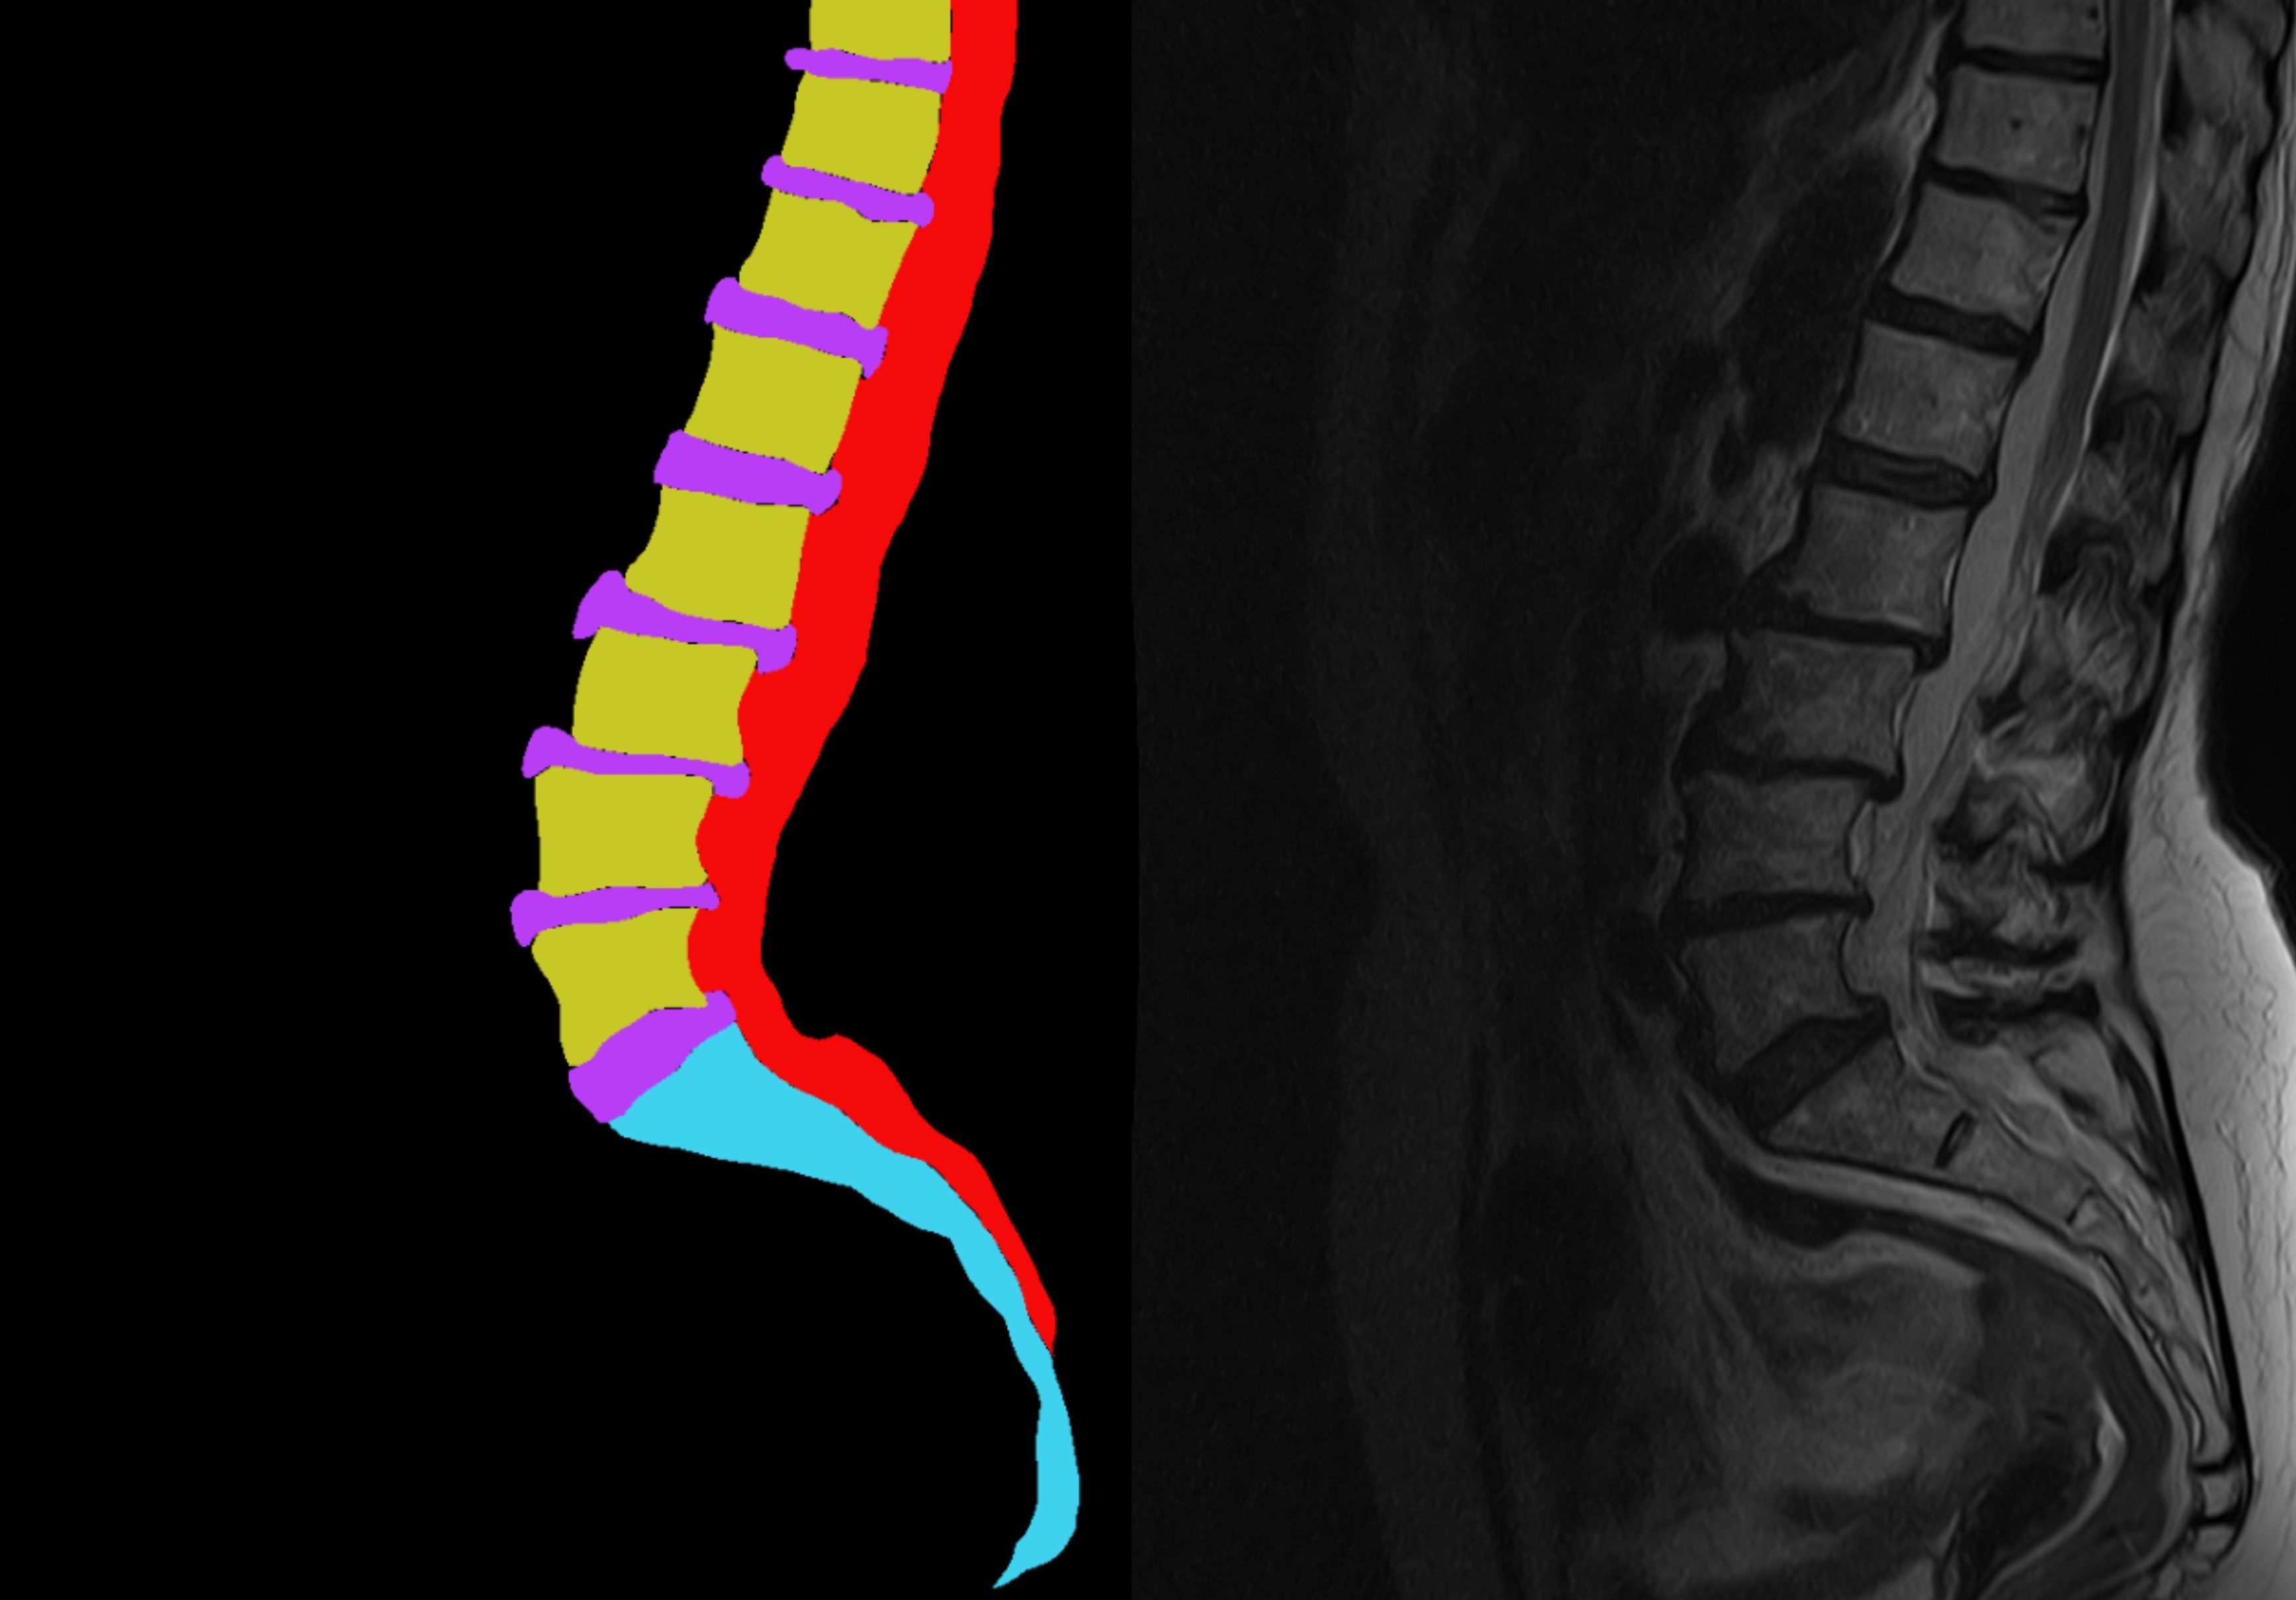

Как разметить 500 000 МРТ-снимков: практический разбор разметки медицинских данных

Методология разметки МРТ-снимков: инструкции, валидация и контроль качества медицинских данных. Опыт NeuroCore.